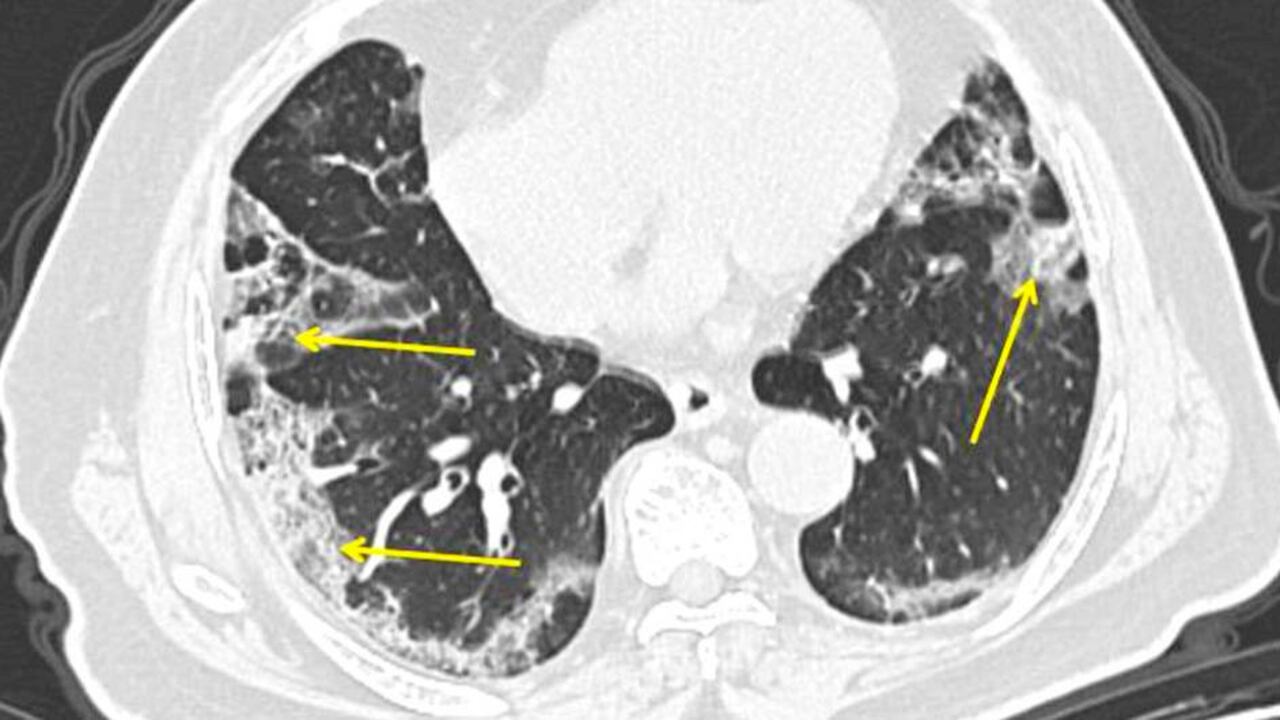

De igual forma, el médico explicó, de manera puntual, el impacto que sufren los pulmones en los pacientes de covid-19: "El revestimiento del árbol respiratorio se lesiona causando inflamación. Esto a su vez irrita los nervios en el revestimiento de las vías respiratorias. Solo una mota de polvo puede estimular la tos”.

“Si esto empeora, va más allá del revestimiento de las vías respiratorias y pasa a las unidades de intercambio de gases, que se encuentran al final de las vías aéreas. Si se infectan, responden vertiendo material inflamatorio en los alvéolos que se encuentran en el fondo de nuestros pulmones”, dijo a The Guardian.

De igual forma, el experto puntualizó que, “una vez que tenemos una infección en el pulmón y, si involucra los sacos de aire, la respuesta del cuerpo es primero tratar de destruir al virus y limitar su replicación”, causa habitual de muerte por neumonía grave entre pacientes con covid-19.